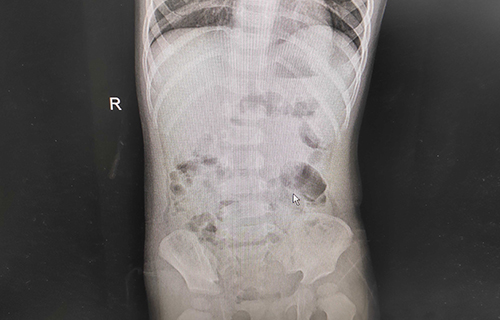

小米妈妈说,孩子发热整整1天,精神萎靡;呕吐2天,平均每天都得吐五六次,呈现非喷射状;腹泻3天,排便呈现水样、蛋花汤样便,尿少。家人急坏了,及时给孩子服用补液盐和双歧三联活菌(益生菌)。在德州扑克游戏网 消化内科诊室内,小米依旧精神不振,并伴有轻度脱水。经查体,小米心肺无明显异常,腹部平软,肠鸣音活跃,神经系统正常。综合查体情况,医生初步诊断其为轮状病毒感染导致的小儿肠炎、轻度脱水。在进行肝功能、肾功能、心肌酶、血离子等检查后,医生发现小米的心肌酶数值异常,提示有心肌损害;血钾3.2mmol/L、血糖3.1mmol/L,均低于正常值。在对症治疗后,小米的临床症状得到极大缓解。